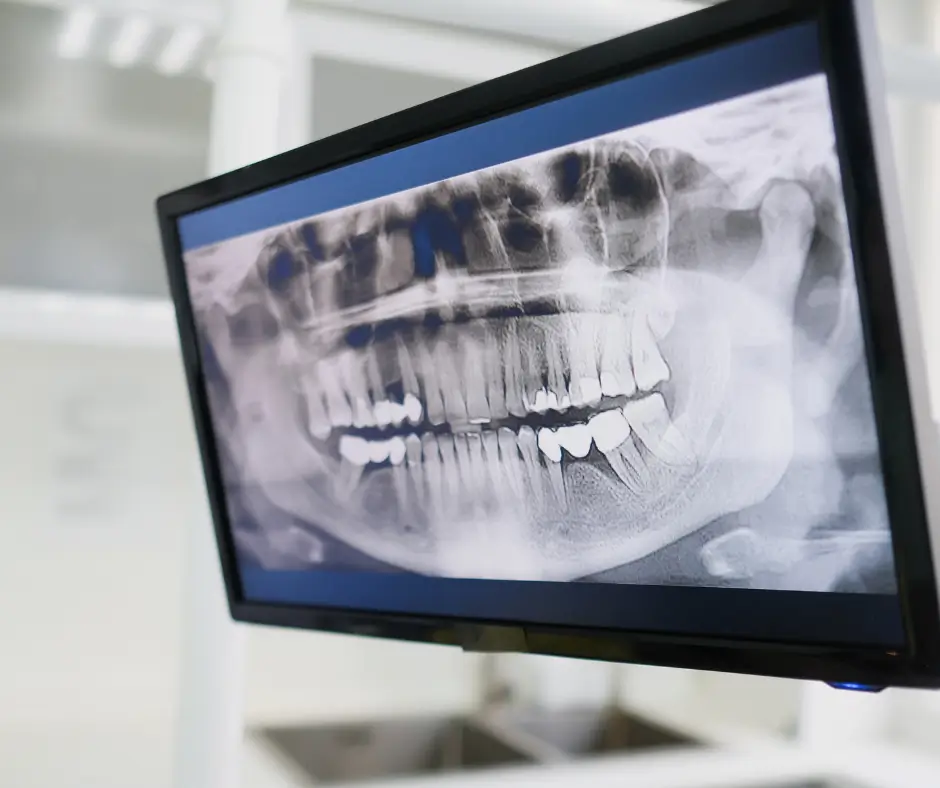

Uno de los pilares fundamentales de los Estudios Ortodónticos Completos es su capacidad para ofrecer un diagnóstico extremadamente detallado. Las imágenes tridimensionales obtenidas a través de tomografías computarizadas y radiografías avanzadas permiten una evaluación exhaustiva de la estructura ósea, la alineación dental y la relación maxilomandibular. Este nivel de detalle no solo identifica maloclusiones, sino que también revela problemas subyacentes que podrían pasar desapercibidos con métodos convencionales.